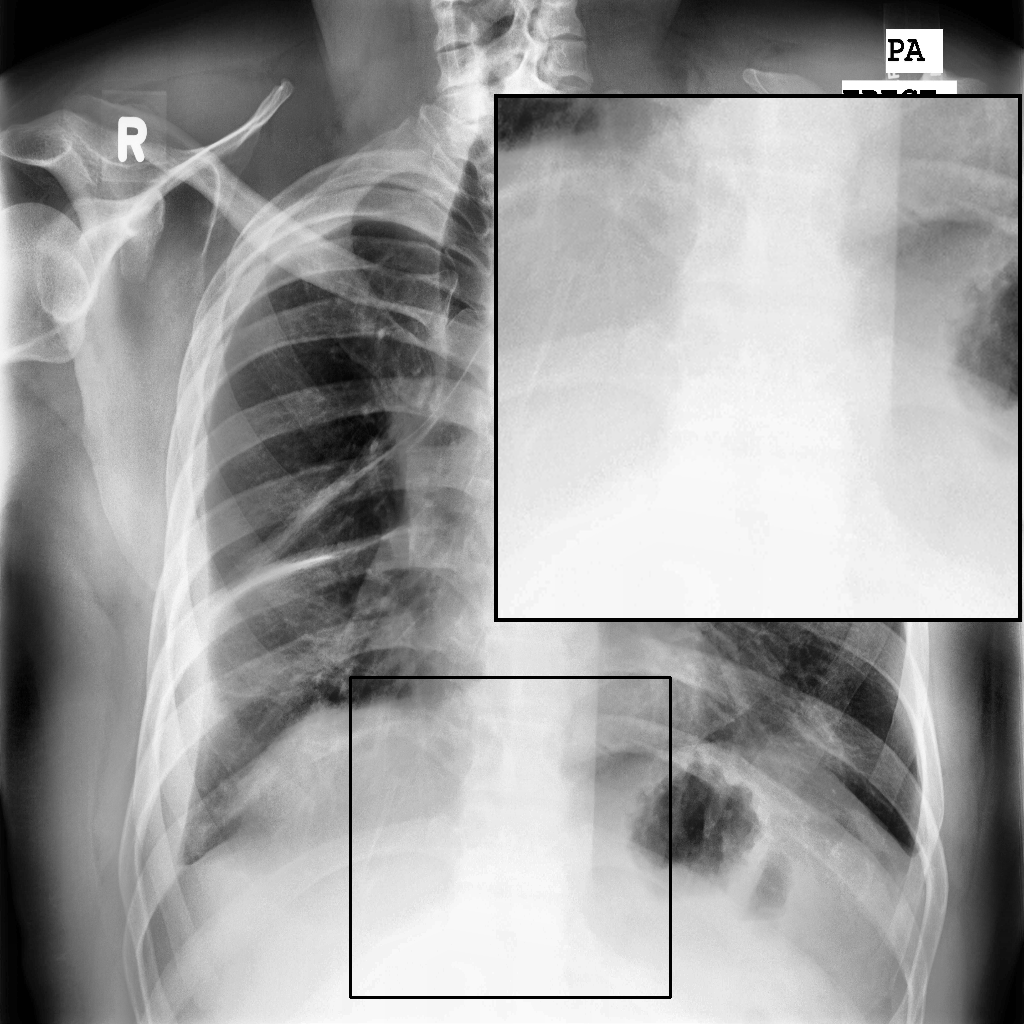

Fig. 3 shows image samples from the above datasets.

Figure 3: Image diversity across four datasets: (a) JSRT, (b) Montgomery County X-ray, (c) NIH ChestX-ray14, and (d) CheXpert